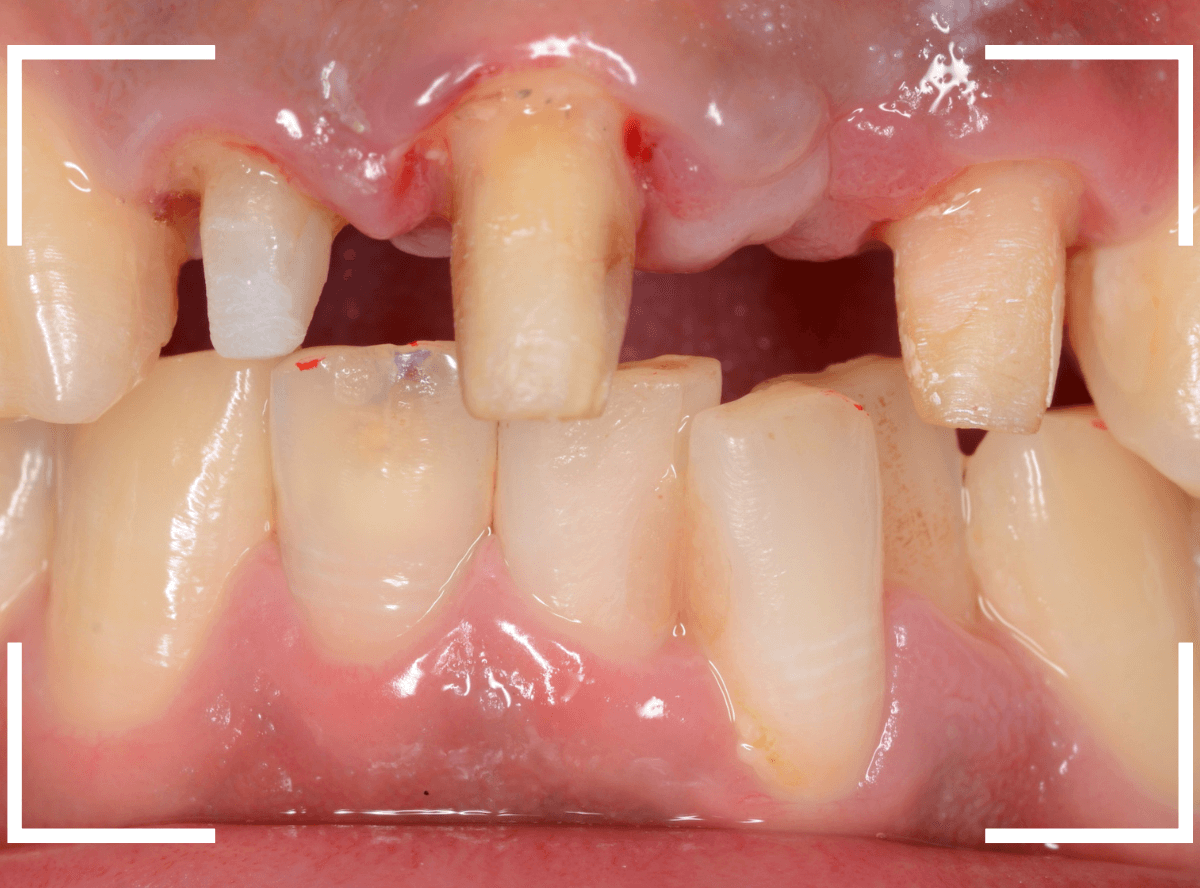

まず、歯周病の治療と並行して、神経の治療を行います。

さし歯を被せるために、歯の土台をたてて、歯を削ります。

歯の高さが低く、このままさし歯を作っても、すぐに取れてしまう事が予想されます。

隣りの歯と比べても歯肉の際が浅いため、若干歯肉を切開して、歯の高さを稼ぎます。

歯肉を切開した部分に、仮歯のレジンを盛って確認します。

大体、隣の歯の高さと合わせる事が出来ました。

しばらく経過観察して、歯肉が落ち着いたところです。

さし歯を入れるのに心配ない程度の歯の高さが確保でき、さし歯を作るための準備が整いました。